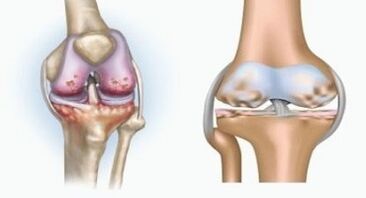

Disease arthritis

Arthritis is an inflammation of connective tissue - a synovial membrane that contains many blood vessels and provides lymphatic flow.The inflammatory process can cause nutrition in the joint tissue to invade the joint lubrication result - synovial fluid is restricted.

Related to joints

Arthritis is a degenerative disease process associated with the destruction of articular cartilage tissue.The cartilage gradually becomes damaged, dry, and the distance between joints and bones decreases, which is the cause of the pain.In severe form, damage can affect the bones.They become more porous, lose their density, and become vulnerable.

For example, what is the difference between knee arthritis and arthritis?Through arthritis, the synovial shell of joint tissue occurs.This can cause joint temperature to rise.

Joint swelling, a persistent pain syndrome development, exacerbates during exercise.With arthritis, pain only occurs after physical activity, and you can hear characteristic tightening or clicking in the joints, gradually deforming and losing mobility.